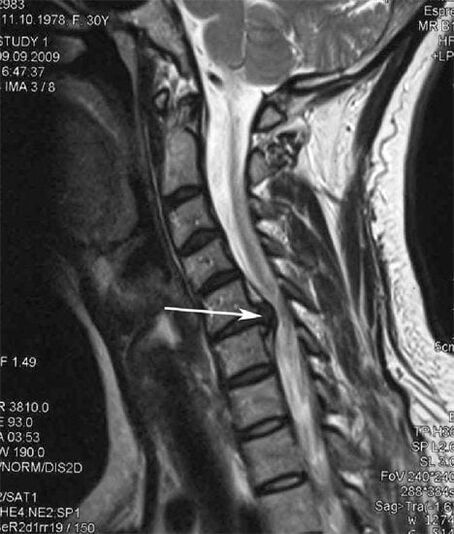

In the initial stages, osteochondrosis is detected using MRI.Later, pathology can be diagnosed using radiography.On radiographs of the cervical spine, a decrease in the distance between the vertebrae, pathological changes in the facet joints, and osteophytosis become noticeable.

Many people complain that they cannot turn their neck due to severe pain that appears after suddenly lifting something heavy.This phenomenon indicates the formation of a herniated disc.The cause of pain in the back, neck and upper limb is pinching of one of the nerve roots emerging from the spinal cord.

| Cervical osteochondrosis | The appearance of pathological changes in one or more spinal motion segments.Impaired spinal mobility, development of myofascial pain syndromes and pinching of spinal roots | Pain, paresthesia and motor disturbances in the cervical region, which spread to the back of the head and upper limbs.Detection of characteristic changes in the spine on MRI and radiographs (osteophytes, decreased distance between vertebrae, signs of damage to intervertebral joints) |